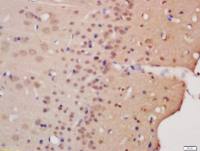

WB, ICC, IHC-P, IHC-F, ELISA

甲状旁腺激素(PTH)多克隆抗体